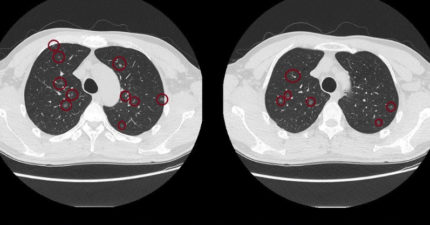

才50歲!男無症狀做健檢 斷層震驚醫:肺結節上百顆